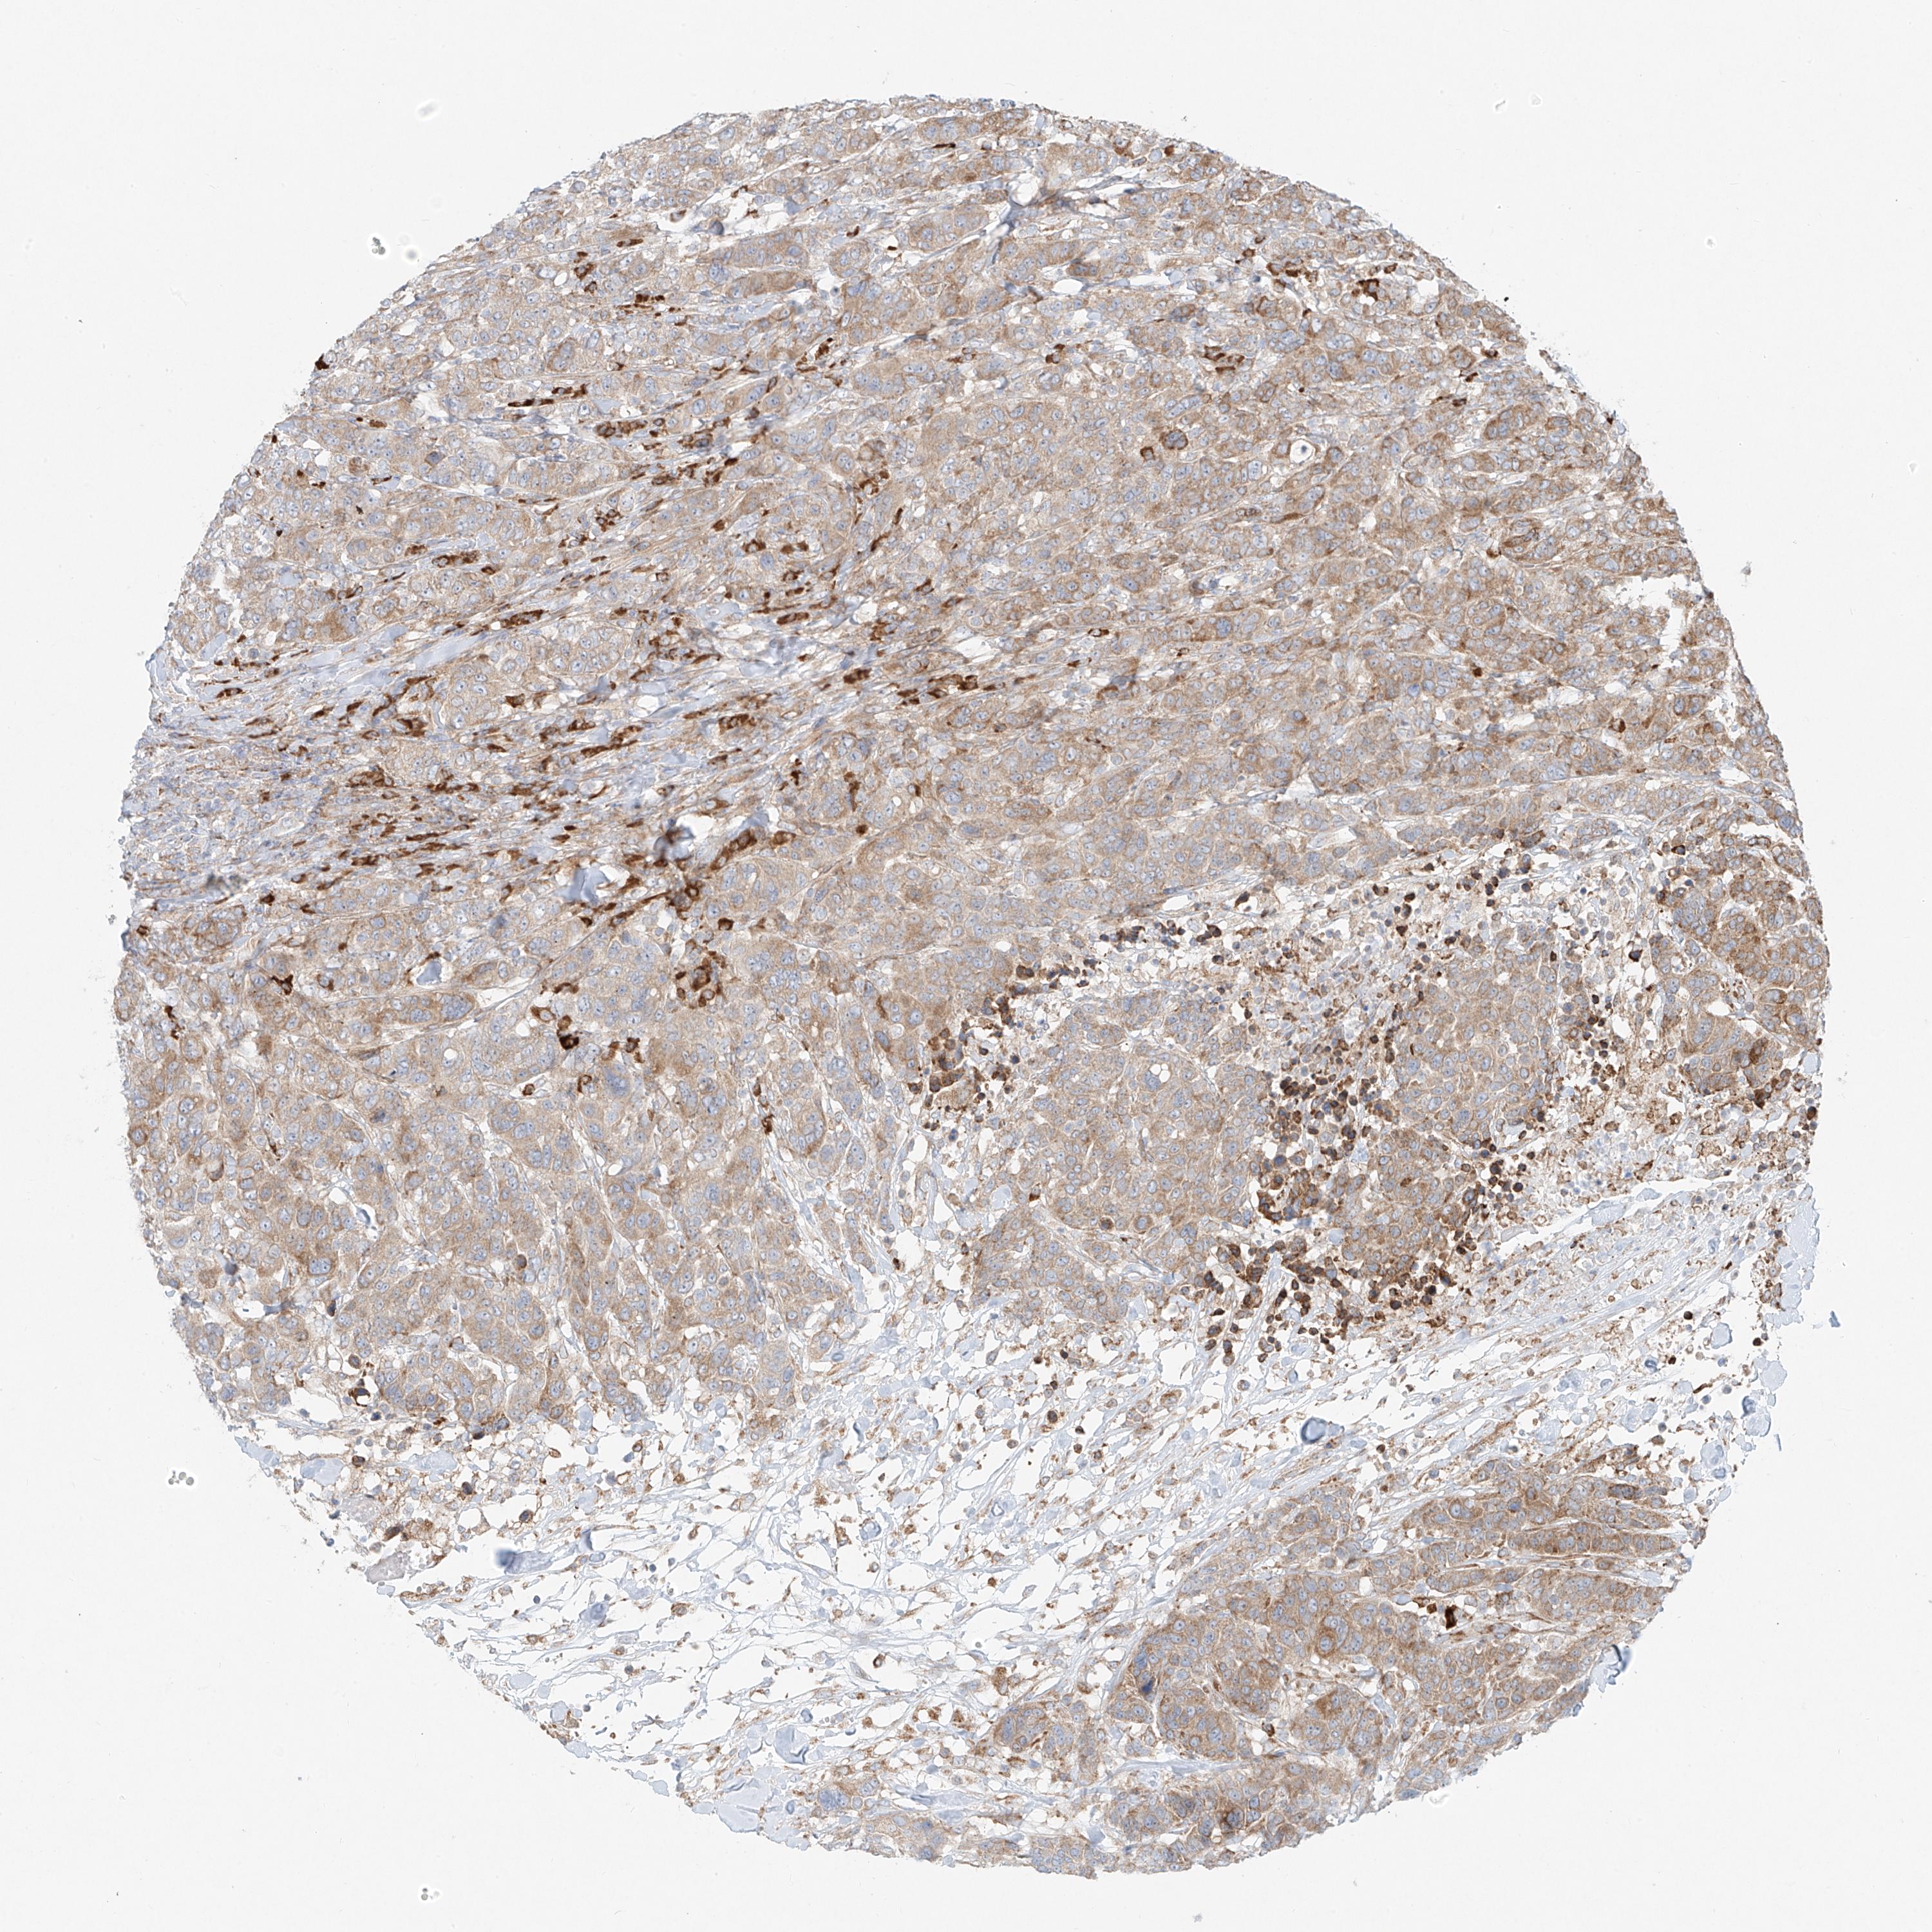

CANCER BREAST CANCER Show tissue menu

BRCA TCGA BRCA VALIDATION PROTEIN EXPRESSION

EIPR1 is not prognostic in Breast Invasive Carcinoma (TCGA)